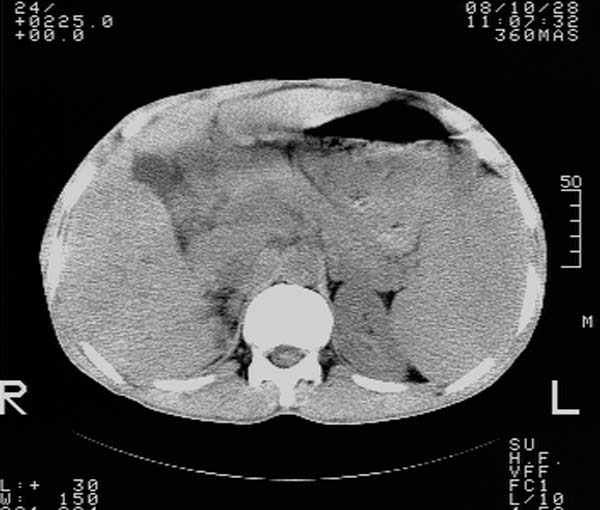

m,65y。半年前发现颈小结节,逐渐增多增大,现双侧耳后、颌下及颈部表浅淋巴肿大。胸片示双肺门增大。外院曾穿刺诊断为淋巴结核。在我科作胸腹部ct,我们觉得外院病检有误。现将图像上传请战友讨论。

纵隔内及腹膜后广泛淋巴结肿大,脾大,肝内似可见低密度影,结合病史半年前发现颈小结节,逐渐增多增大,现双侧耳后、颌下及颈部表浅淋巴肿大。考虑淋巴瘤。

我们也是首先考虑淋巴瘤。只是外院病检报告是结核。让人迷惑。肝左叶多发低密度占位,没增强不好定论。

纵隔,双肺门腹膜后多发淋巴结重大,非融合,肝脾轻度肿大,双肺野弥漫性小结节;考虑淋巴瘤,结节病可能性

纵隔内,双肺门、腋窝及腹膜后多发肿大淋巴结影,肺内小结节影,肝脾体积增大,支持淋巴瘤。肝内多发低密度影,考虑小囊肿。

考虑淋巴瘤肺、肝内转移,脾脏肿大。

纵隔内,双肺门、腹膜后多发肿大淋巴结影及颈部淋巴结肿大,肝脾体积大.结合临床,淋巴瘤可能性大。